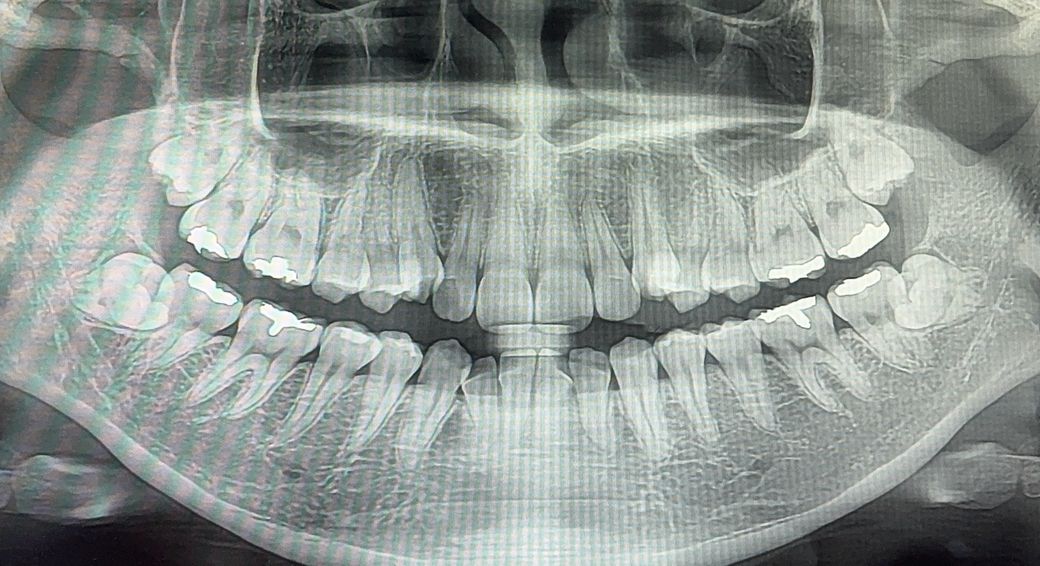

치아 뿌리 많이 짧은가요? (교정하는 중입니다)

교정 장치 붙이기 전 엑스레이고, 교정기는 그저께 위에만 붙였어요

치아 뿌리 많이 짧은 편인가요? 턱이 작다고 하시긴 했는데 선천적인 걸까요..

의사쌤은 별말 없으셨는데 인터넷 찾아보니까 제 뿌리가 짧은 것 같아서요.. 치근흡수?가 걱정되네요

치아 뿌리 말씀드리면서 앞니 교정력을 약하게 해달라고 말씀드려야 할까요?

엑스레이 상으로 아래 앞니 치아뿌리가 상대적으로 짧아보이긴합니다. 하지만 엑스레이 촬영에 따라 다르게 보일수 잇습니다.

2. 파노라마 사진이 원래 앞니 뿌리 부위는 살짝 왜곡을 일으켜 보이기도 합니다. 그래서 정확한 판단은 어려운데 살짝 평균보다 치근이 짧아보이긴 합니다.

3. 이와 관련해서 우려되는 점을 교정 담당 치과의사에게 말해도 좋습니다.